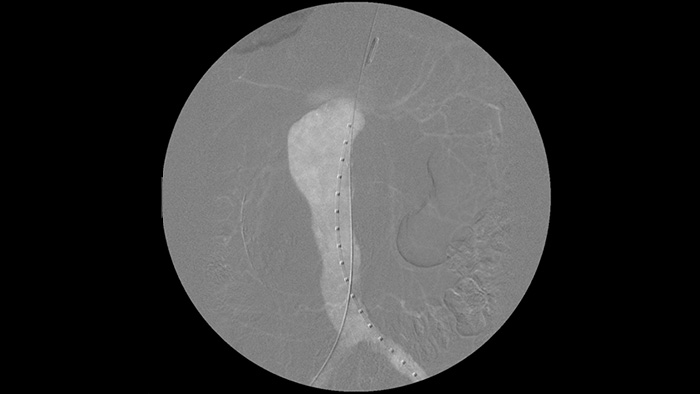

A angiografia de subtração digital (DSA) é utilizada em procedimentos vasculares de intervenção para visualizar claramente os vasos sanguíneos através da remoção de estruturas que possam obscurecer a visibilidade dos vasos. A fluoroscopia de mapeamento sobrepõe uma imagem de contraste subtraída adquirida anteriormente na fluoroscopia em tempo real, permitindo-lhe monitorizar um dispositivo sem reinjetar contraste.

Melhore a visibilidade do sistema vascular tortuoso com as opções de contraste de iodo e CO2. Controle facilmente as injeções junto à mesa. Para pacientes com insuficiência renal, pode utilizar a opção de CO2 para visualizar facilmente vasos pequenos sem utilizar o contraste de iodo.